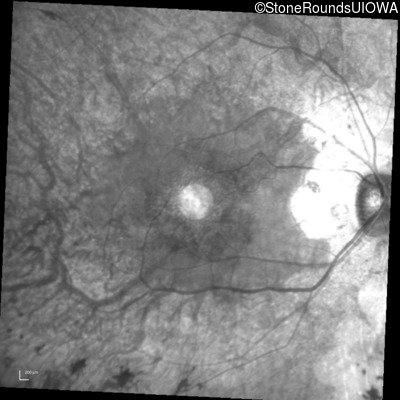

Infrared Fundus Photograph - Right - 20/25 -2 sc

Exemplar